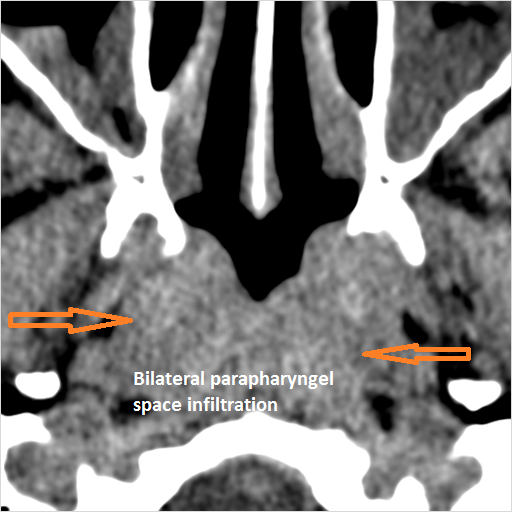

There is evidence of inflammatory changes within the parapharyngeal fat of the nasopharynx. [Yes/No]